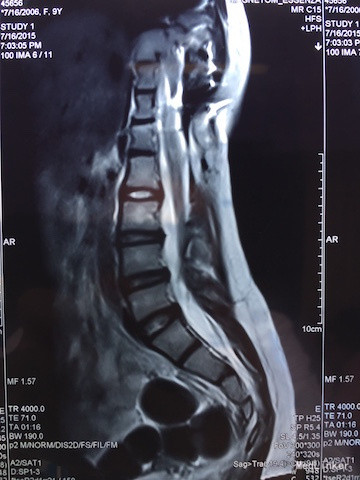

查体:四肢感觉、肌力及肌张力无明显异常,直腿高抬试验(-),双侧足背动脉搏动良好,腰椎活动可,病理征(-)。 辅助检查:胸腰椎MRI(如下图):脊髓下段受牵拉平对第3腰椎下缘,合并脊柱旁占位及脊柱裂可能。

诊断:脊髓栓系综合征 治疗:脊髓栓系松解术

随访与讨论:手术顺利,术后神经受牵拉症状需至少半年才能恢复。诊断及鉴别诊断:脊髓栓系综合征:是由多种脊髓先天性发育异常导致的系列临床综合征。脊髓下段因各种原因受制于椎管终末端,使其位置低于正常。根据该患者临床表现及影像学检查,考虑可能性大。马尾综合征:大多是由于各种先天性或后性原因之腰椎管绝对或相对狭窄,压迫马尾神经而产生一系列神经功能障碍,可有会阴区感染异常及大小便失禁,根据该患者影像学检查。